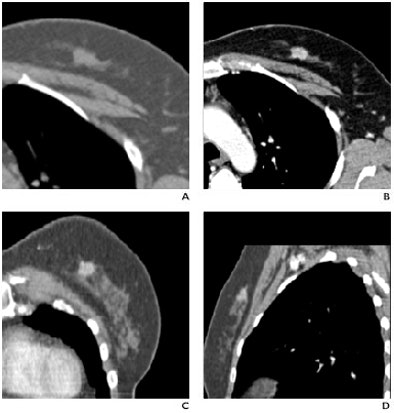

![]()  |

| Fifty-eight-year-old woman with phyllodes tumor in left breast. Dynamic MDCT scans at baseline (left) and one minute after contrast administration (right) show a large, regular lesion with early and intense enhancement in most of the breast. All images courtesy of the American Roentgen Ray Society. |